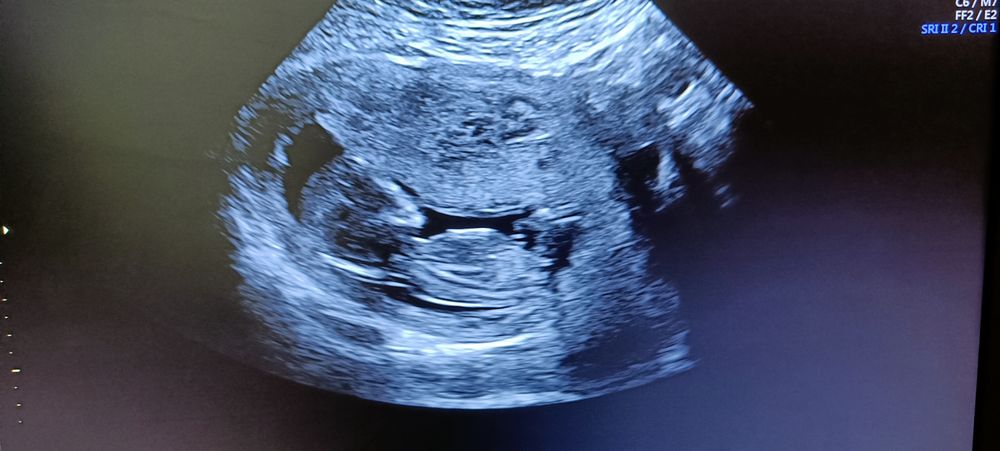

Результаты первого скрининга

Ну все, наконец дождалась! Вроде все норм, я ничего в этом не понимаю, врач сказала, что все хорошо, второй скрининг после 10 октября! Пол не сказали, так что остаётся только гадать 🤷🏼♀️ оставляю все тут на память. Зря переживала по поводу возраста похоже